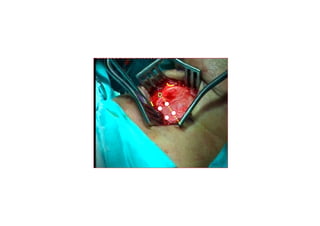

MedializasyonMedializasyon (Tip I)(Tip I) tiroplastitiroplasti

TTiroidiroid kk kk rdakta ardakta açç lanlan penceredenpencereden

yerleyerle((tirilen birtirilen bir implantimplant aracarac ll ileile

VFVF’’ unun medialmedialee itilmesiitilmesi

5 mm

PreopPreop

PostopPostop

1. hafta1. hafta

3. ay3. ay